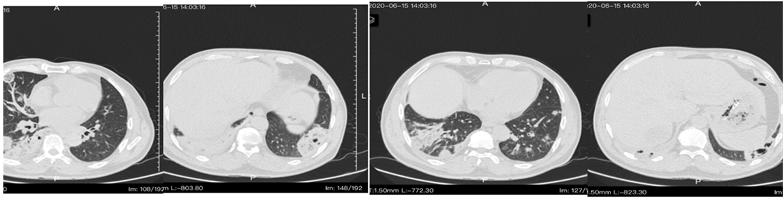

肝脓肿引流(图三)